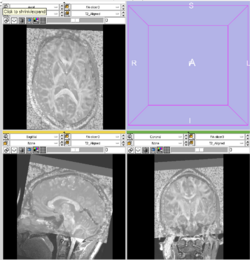

T1 to Average Gradient Affine Registration

Results using slicer2

Results using slicer3 as of 2008-04-10

• Reference 'Gold Standard'

• Slicer2 calculation using Mattes MI Affine (also uses ITK implementation)

• Result transform:

0.950655 0.024335 0.0259082 0.857786

0.0086567 0.8889 -0.379321 -6.77365

-0.0395529 0.39257 0.835359 14.664

0 0 0 1

• Software

• Slicer3 svn trunk 2008-04-10

• Parameters

• Defaults

• Method

• Use T1 as fixed, Gradient as moving

• Results 2008-04-10

• Cannot run due to sampling issue

itk::ExceptionObject (0x1990140)

Location: "void itk::MattesMutualInformationImageToImageMetric<TFixedImage, TMovingImage>::GetValueAndDerivative(const typename itk::ImageToImageMetric<TFixedImage, TMovingImage>::ParametersType&, typename itk::ImageToImageMetric<TFixedImage, TMovingImage>::MeasureType&, typename itk::ImageToImageMetric<TFixedImage, TMovingImage>::DerivativeType&) const [with TFixedImage = itk::OrientedImage<short int, 3u>, TMovingImage = itk::OrientedImage<short int, 3u>]"

File: /Users/pieper/slicer3/latest/Slicer3-lib/Insight/Code/Algorithms/itkMattesMutualInformationImageToImageMetric.txx

Line: 1036

Description: itk::ERROR: MattesMutualInformationImageToImageMetric(0x198d470): Too many samples map outside moving image buffer: 2481 / 10000

ERROR: In /Users/pieper/slicer3/latest/Slicer3/Modules/CommandLineModule/vtkCommandLineModuleLogic.cxx, line 1326

vtkCommandLineModuleLogic (0x1d265ac0): Affine registration completed with errors